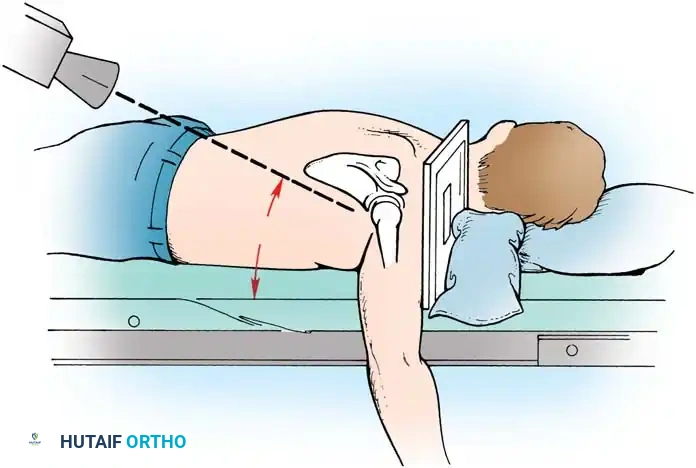

Patient Positioning and Anesthesia

The procedure is typically performed under general anesthesia supplemented with an interscalene regional nerve block for postoperative analgesia. The patient is placed in the beach-chair position with the head secured and the operative arm draped free to allow full manipulation. A mechanical arm holder is highly recommended to control rotation and abduction during the capsular shift.